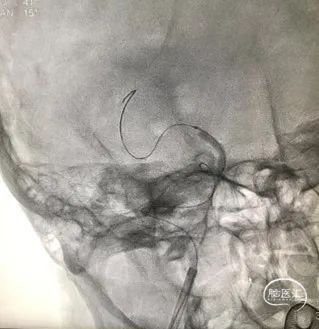

球囊扩张过程

扩张后造影